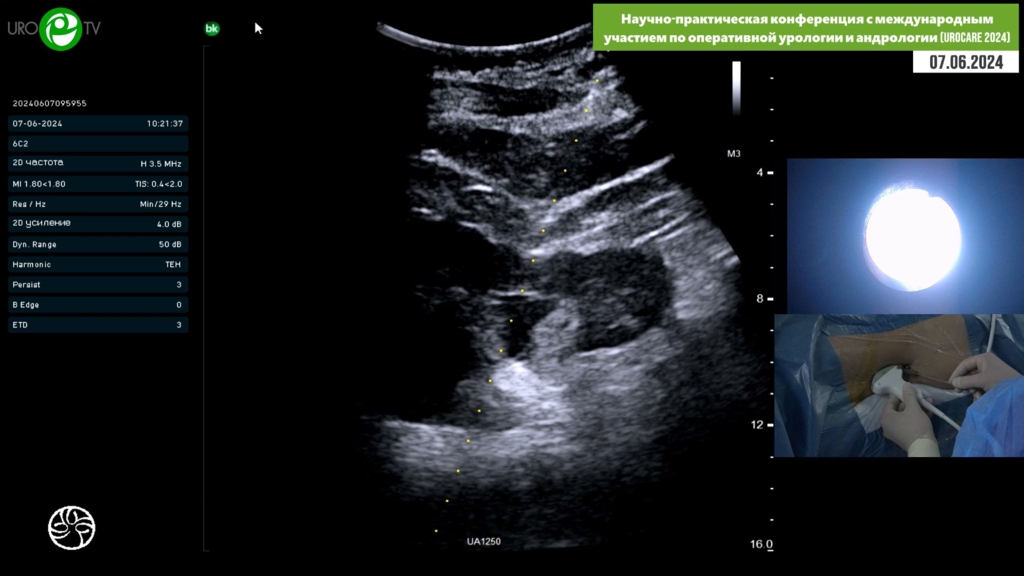

Панферов А.С. - Перкутанная нефролитотрипсия

27 июн 2024

Мочекаменная болезнь